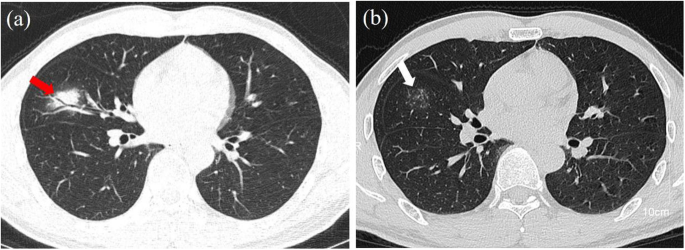

A male patient infected with SARS-CoV-2. a The first CT was performed three days after the onset of symptoms. The chest CT image shows single consolidation in the right middle lobe and air bronchogram (red arrows). b The second CT was performed 13 days after the treatment. The chest CT image shows a tree-in-bud pattern (white arrows)

All the patients underwent CT 1–11 days after admission (median, 4 days). There were 54 of 67 patients with lesions, and the remaining 13 patients were normal in chest CT images. As shown in Table 2, fifty of the fifty-four patients had lesions in the peripheral regions (Fig. 1), and four patients had lesions in the central areas. Twelve patients had abnormalities in the middle-upper lobe, and the remaining forty-two patients had abnormalities in the middle-lower lobe. There were eight patients with a single lesion (Fig. 2(a)) and 46 patients with multiple lesions (Fig. 1). Forty-two of the fifty-four patients had ground-glass opacities (Figs. 1, 2, 3, 4), and twelve patients had isolated consolidation (Fig. 2(a)). Interlobular septal thickening was identified in eleven patients. Reversed halo sign was noted in nine patients. There were eighteen patients with air bronchogram. Three patients had bronchial wall thickening. Tree-in-bud pattern was identified in one patient (Fig. 5(a)). Air cavities were present in four patients (Fig. 3). Pleural thickening or pleural effusion was noted in fourteen patients. Only two patients had intrathoracic lymph node enlargement (Fig. 4 (d)).